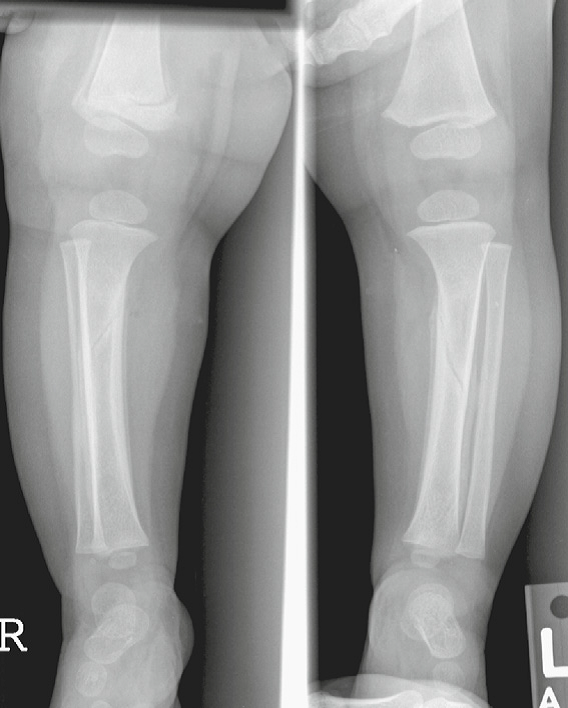

Toddler’s fracture

• When a child first begins to walk

• A nondisplaced oblique or spiral fracture of the midshaft

of the tibia

• Most children present with failure to continue to walk or refusal to bear weight on that extremity

Common sites for Toddler’s fracture

• tibial midshaft

• proximal anterior tibia

• calcaneus

• cuboid